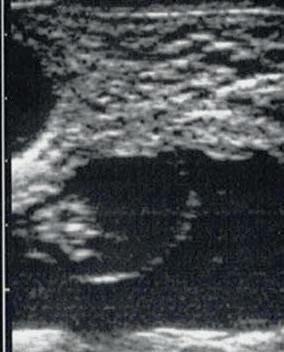

• Sombra Acústica: Se conoce con este nombre a una zona de menor brillo que se produce como consecuencia de que llega una menor cantidad de ondas de ultrasonido a la zona por haber sido reflejados en las capas más superficiales.

Sombra acústica (rojo degradado) en una imagen de un feto.

La exploración ecográfica de los ovarios nos permite diferenciar fácilmente las estructuras fisiológicas presentes. Así veremos que los folículos aparecen en la imagen como estructuras más o menos circulares y negras, que no suelen hacer prominencia en la superficie del ovario. Por contra, las estructuras luteínicas presentarán una imagen de un tono gris oscuro, con una forma circular y en la mayor parte de los casos apreciaremos una cabeza, más o menos evidente, que hace una prominencia en la superficie ovárica. En el interior de esta estructura luteínica puede verse una pequeña cavidad con líquido (anecogénica) o bien una especie de banda blanca (hiperecogénica) que atraviesa el cuerpo lúteo de un lado a otro (travécula).